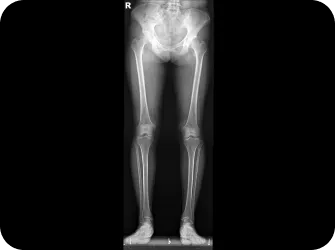

다리길이 엑스레이 검사